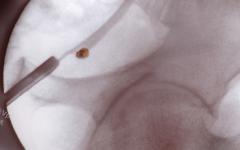

Хомеопатия при бъбречни кризи

Когато малко камъче тръгне по пикочните пътища, обикновено причинява бъбречна криза. Много са тези, които познават болките – силни, спастични, като колика – засилват се и отслабват. При слаб удар в областта на болния бъбрек стават нетърпими.